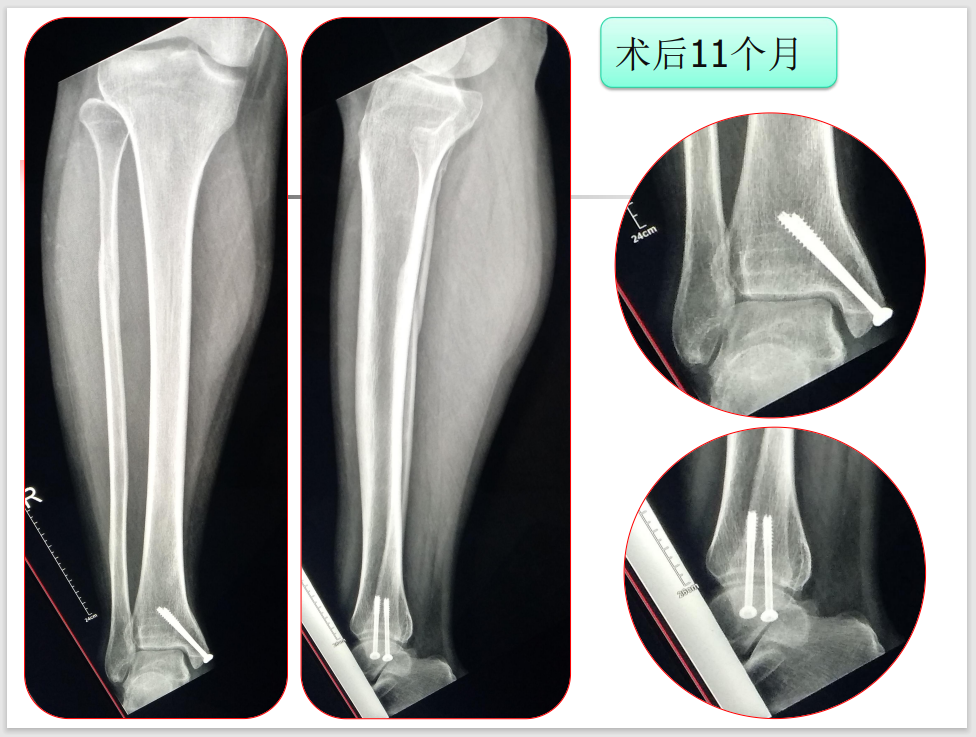

术后11个月,步态良好,无不适感